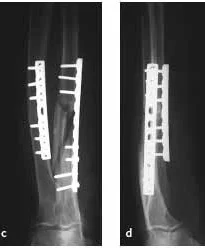

Forearm Fractures

- (Considered as a joint)

- Management:

- Undisplaced:

- Possible conservative - cast & follow up

- Displaced:

- Anatomical Open reduction and internal fixation by Plating and screws( best fixation)

- Early motion - Prevents stiffness

Galeazzi Fracture/ Dislocation

Fracture of the radius with dislocation of the distal radio-ulnar joint

“Fracture of necessity”

- Necessitates surgery

“Fracture of necessity”:

- Plating of radius

- Reduction of distal radio-ulnar joint (+/- Fixation)